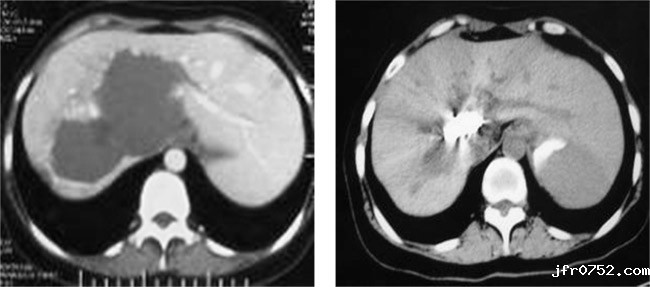

以下是成功病例的CT影像对比:

女,46岁,肝门区巨大海绵状血管瘤,肝动脉栓塞及经皮穿刺平阳霉素碘油乳剂注射,治疗后肿瘤完全消失。